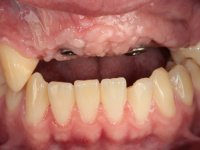

Paciente do sexo masculino, com 22 anos de idade e não fumador. Apresentou-se na consulta 6 meses após um acidente de viação em que perdeu os dentes 21, 22, 23 e 24. Os dentes 12 e 11 apresentavam mobilidade grau 3 apresentando-se também com extracção indicada. A arquitectura gengival da zona desdentada apresentava-se retraída e planificada.

O paciente foi observado conjuntamente e a dúvida que surgiu de imediato foi se seria possível com a regeneração óssea a efectuar poder ser reabilitada naturalmente a zona das papilas interdentárias. Nesse sentido foi feito um enceramento de diagnóstico que contemplaria as duas hipóteses, utilizando ou não a cerâmica gengival. A confecção desse enceramento foi fundamental para expor ao paciente a dificuldade da reabilitação. O wax-up deu origem a um mock-up que foi aprovado pelo paciente e que simultaneamente serviu de guia imagiológica. O caso foi planificado cirurgicamente e realizada uma guia cirúrgica com que foram colocados os implantes. Após 10 semanas foi feita a 1ª impressão para confecção da ponte provisória. Foram criados os primeiros perfis de emergência na gengiva artificial e foi digitalizado o modelo. Por processo de CAD-CAM foi confeccionada uma ponte provisória aparafusada baseada no enceramento de diagnóstico. A ponte trabalhou durante 8 semanas os tecidos moles que foram fielmente copiados numa impressão com técnica de moldeira aberta. Os transferes foram individualizados com resina composta para copiarem fielmente os perfis de emergência criados pela ponte provisória. Confeccionado o modelo de trabalho definitivo, foi realizada uma infra-estrutura em zircónio seguindo a orientação do enceramento de diagnóstico. O assentamento da infra-estrutura foi testado em boca e simultaneamente foi novamente impressionados os tecidos moles com um silicone fluido. Nessa consulta foi feito o levantamento da cor. Os dentes 13 e 23 apresentavam uma saturação anormalmente forte que resolvemos não valorizar, optando por privilegiar a relação com o sector antero-inferior. Foi realizada uma nova gengiva artificial com a impressão que acompanhou a impressão de arrasto com a infra-estrutura. Após a colocação da cerâmica na infra-estrutura foram coladas as meso-estruturas. O trabalho final foi aparafusado lentamente permitindo a adaptação dos tecidos moles.